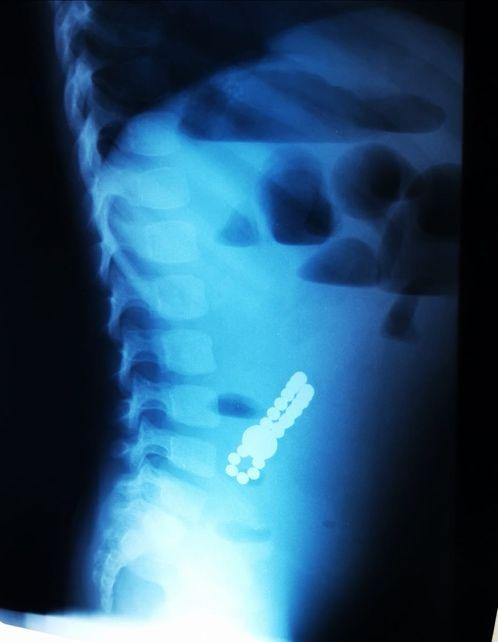

„Acești magneți sunt foarte puternici, iar ingestia lor poate duce la probleme gastrointestinale grave. Odată înghițiți sunt atrași unul spre altul chiar dacă se găsesc în secțiuni diferite ale tubului digestiv. O ansă intestinală prinsă între acești magneți se poate perfora ducând la tratament chirurgical de urgență. În secția noastră, de la începutul anului s-au prezentat trei cazuri, două fete și un băiat, cu vârste cuprinse între 2 și 4 ani.

Aceștia au suferit perforații la nivelul intestinului subțire și au necesitat intervenții pentru îndepartarea porțiunii de intestin afectate”, a precizat dr. Adriana Constantineanu.